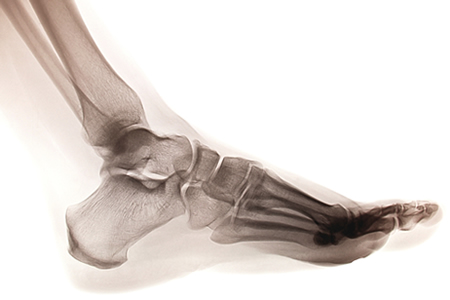

Ankle Sprains

Ankle Sprains Physical Therapy NYC

A lateral (outside) ankle sprain is perhaps the most common sports injury. With a sprained ankle the surrounding musculature tightens like a splint to protect the damaged ligaments. This places strain on these muscles that can impair function long after the pain and swelling subside. Ligaments can be slackened, leaving the joints less stable. Worse still, balance and stability can be compromised long-term.